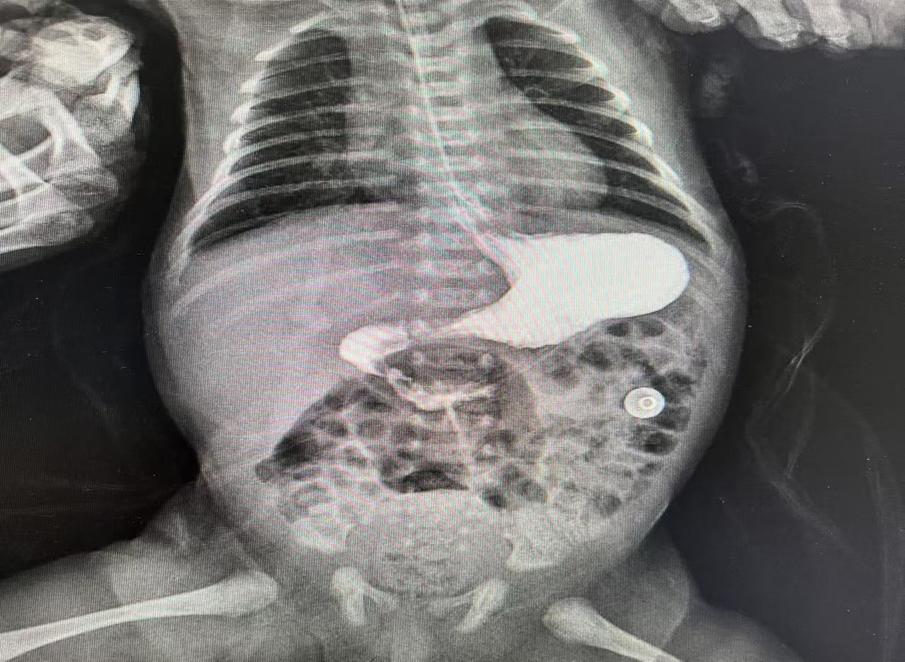

圖片10.jpg

術(shù)后復查十二指腸已通暢